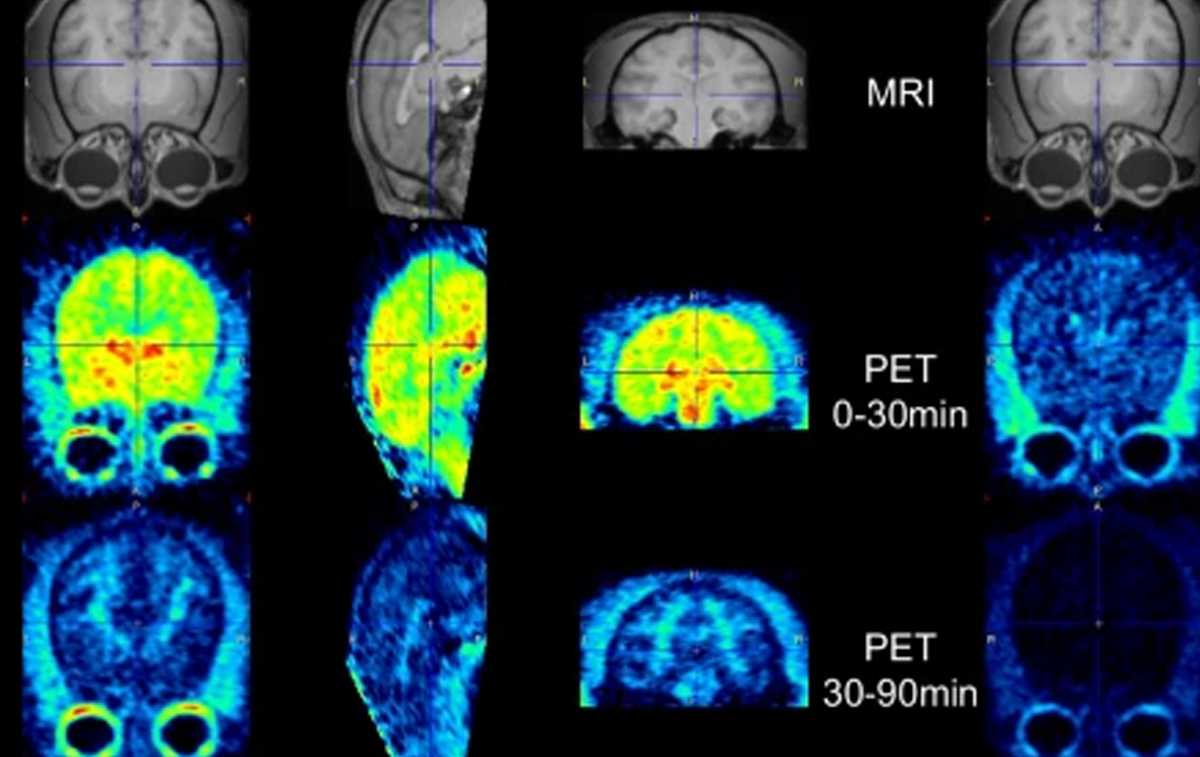

Through extensive validation in postmortem human tissue, cellular systems, and non-human primates, both ligands demonstrate high affinity for pathological TDP-43 aggregates with strong selectivity over common co-pathologies such as amyloid-β, tau, and α-synuclein. Favorable brain uptake and rapid washout profiles support clinical translation, with [18F]ACI-19626 prioritized for first-in-human studies. Together, these first-in-class tracers offer a powerful new tool to visualize TDP-43 in vivo—opening opportunities for earlier diagnosis, patient stratification, and precision therapeutic development across the ALS-FTD spectrum and related proteinopathies.

• Shows translational readiness, including favorable pharmacokinetics and brain penetration in non-human primates